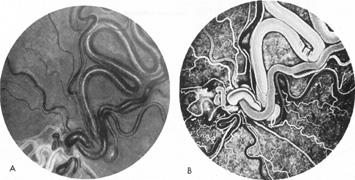

Tortuous or redundant basilar arteries are not uncommon in the older age group. Occasionally, gross dilation or ectasia develops so that the basilar artery acts as a mass in the posterior fossa. This phenomenon produces signs of low-pressure hydrocephalus, cranial nerve palsies, and long tract and sensory signs and may even simulate a cerebellopontine angle tumor or tumor at the foramen magnum.58 It is possible to diagnose such lesions with CT59 or MRI60 but angiography is definitive (Fig. 6). The association of insidious multiple cranial nerve palsies and long tract signs referable to a brainstem level, in an elderly patient with evidence of atherosclerosis, should make fusiform basilar artery dilation a diagnostic consideration.

Fig. 6. Fusiform basilar dilation. A: Lateral projection vertebral arteriogram showing a widened basilar artery (arrow) projecting beyond level of dorsum sellae. B: Anteroposterior projection showing a widened and tortuous basilar artery.